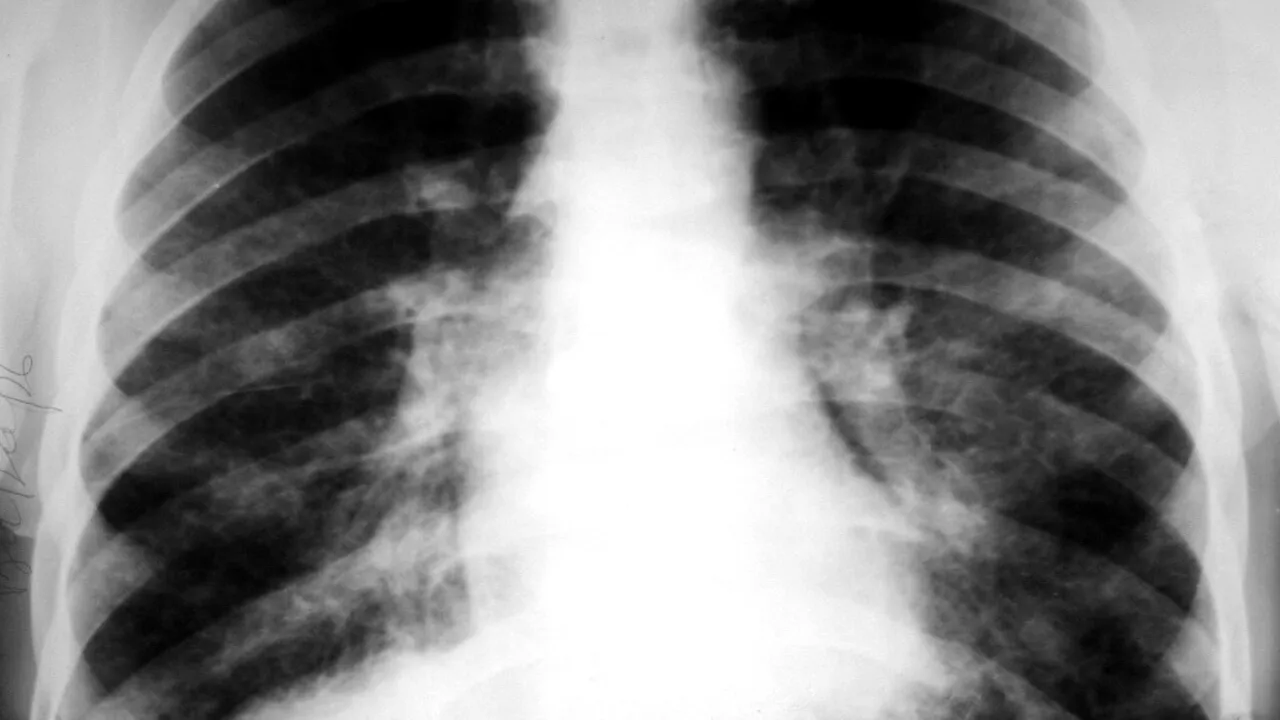

De la începutul anului, tot mai mulți români s-au îmbolnăvit de neoplasm pulmonar. Medicii pneumologi din cadrul Spitalului Clinic Judeţean de Urgenţă Arad trag un semnal de alarmă cu privire la numărul mare de pacienţi diagnosticaţi cu neoplasm pulmonar.

Aproape un sfert dintre cei care şi-au făcut bronhoscopii au primit acest diagnostic, arată cadrele medicale de la SCJU Arad.

De la începutul acestui an, la Arad, medicii specialişti au descoperit 30 de cazuri cu neoplasm pulmonar la 120 de pacienţi care şi-au făcut bronhoscopii.

Pentru a se depista afecţiunile pulmonare în stadii incipiente, doctorii recomandă examinările periodice. Motivul e simplu: „Plămânii au puţini receptori ai durerii, iar simptomele apar, adeseori, în stadii avansate ale bolii”.

La Arad, efectuăm această procedură din luna ianuarie, iar până acum au fost realizate 120 de bronhoscopii. Ţesuturile suspecte extrase sunt trimise mai apoi spre analiză la laborator, rezultatul fiind eliberat între 14 şi 21 de zile. Până acum am efectuat 35 de biopsii, iar din păcate, în cazul a 30 dintre acestea diagnosticul a fost de neoplasm”, a explicat dr. Erika Repolski, medic primar pneumolog.

Medicii recomandă persoanelor care au dureri în zona pieptului, respiraţie greoaie, tuse prelungită (uneori cu sânge), voce răguşită, infecţii pulmonare dese și acuză o lipsă a poftei de mâncare, însoţită de pierdere rapidă în greutate, să se prezinte de urgență la un medic pneumolog.